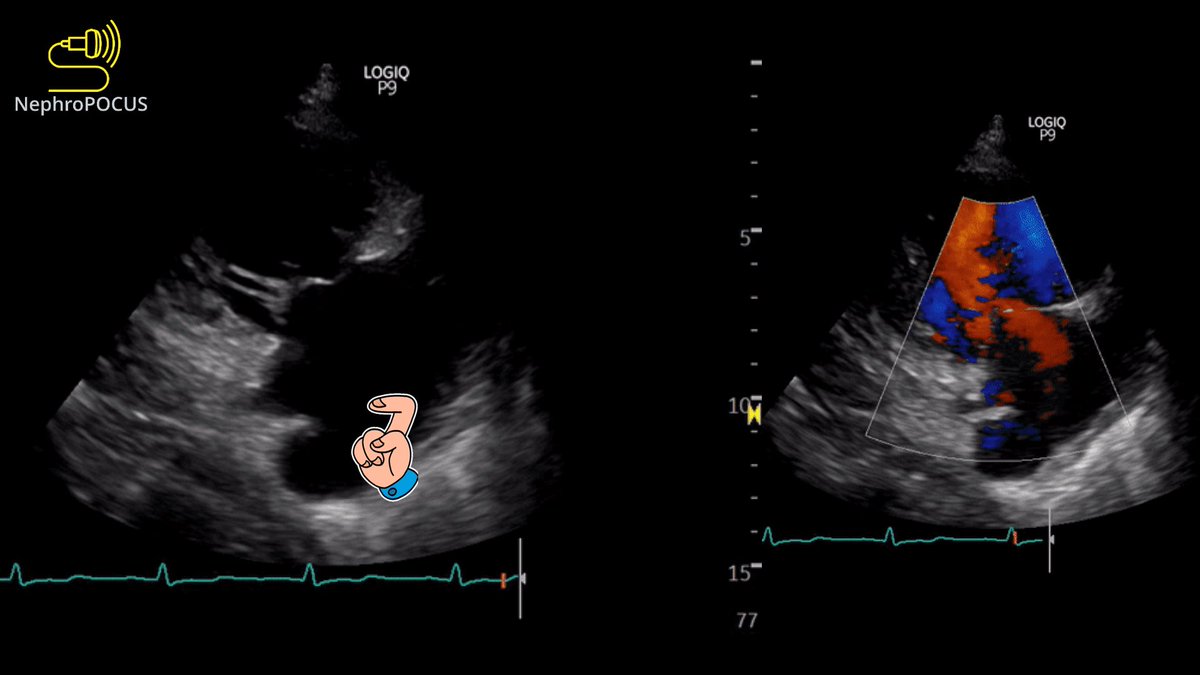

1⃣ What transthoracic #echofirst view is this?

2⃣ What is the structure indicated by 👈